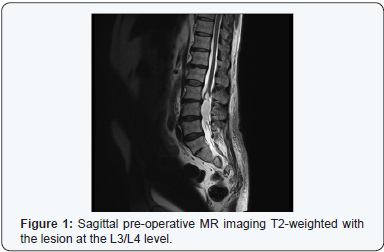

The Magnetic Resonance (MR) image of the patient’s spine showed there to be an intradural extramedullary mass lesion centered at the level of L3, below the conus medullaris, and expanding almost the entire length of the L4 vertebra. It was causing significant compression of the cauda equina nerves and was shown to be expanding the conus medullaris (Figure 1).